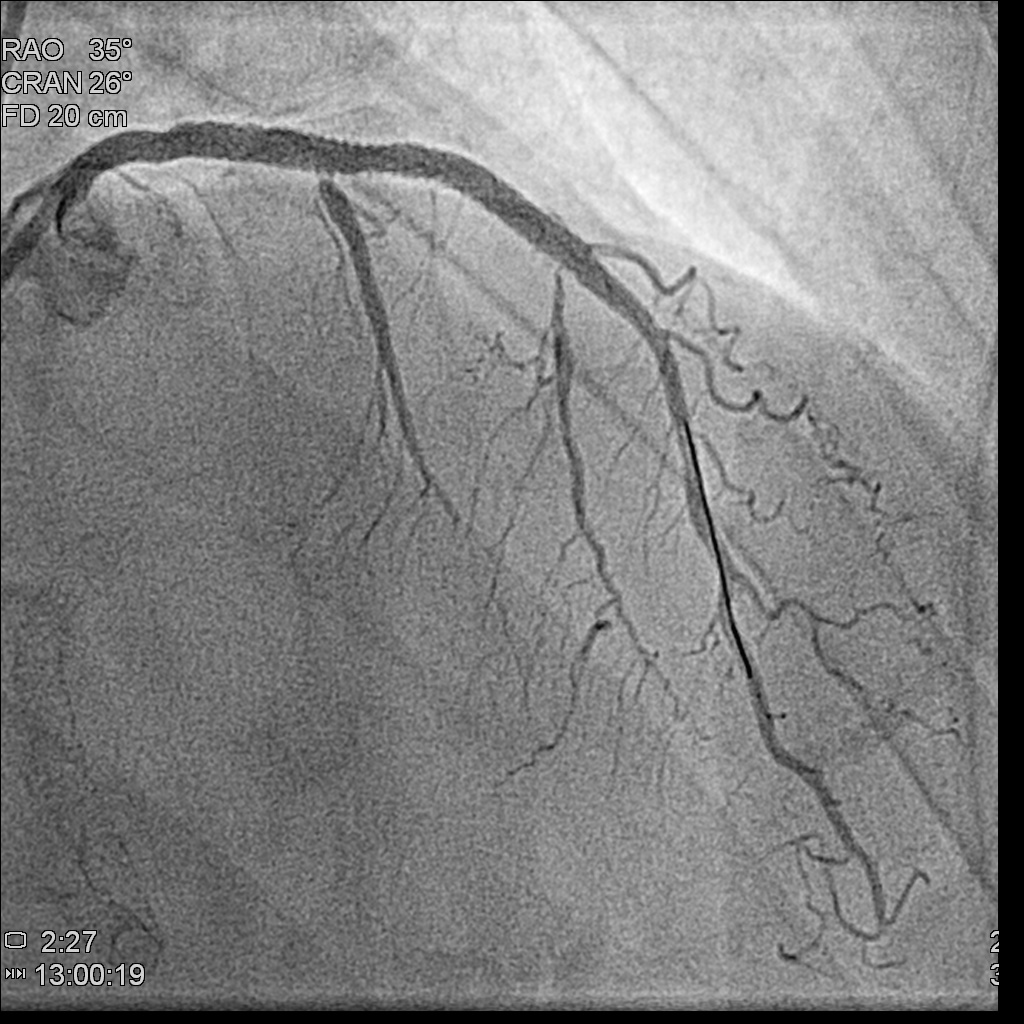

Left main: 50% stenosis at distal left main

Left anterior descending artery: diffuse atherosclerotic plaque,proximal to middle total occlusion, with a big septal branch sending collaterals to distal LAD and distal RCA

Left circumflex artery: absence of LCX from angiography

Left anterior descending artery: diffuse atherosclerotic plaque,proximal to middle total occlusion, with a big septal branch sending collaterals to distal LAD and distal RCA

Left circumflex artery: absence of LCX from angiography

Few months later, we saw the collateral vessels providing RCA previously were all disminished and the RCA flow was fine .We attempted his LM-LAD lesion with Miracle 6 and Gaia II guidewires.The microcatheter successfully entered the LAD stenotic segment. The Gaia II guidewire was negotiated through the point successfully. Dilatation was performed with 2.5x15mm,3.0x30mm Trek balloons sequentially. A Synergy 3.5x48mm DES was deployed from the middle left main (LM) to the middle LAD, followed by post-dilatation with 4.5x15mm NC Euphora balloon. The final result showed acceptable results

Few months later, we saw the collateral vessels providing RCA previously were all disminished and the RCA flow was fine .We attempted his LM-LAD lesion with Miracle 6 and Gaia II guidewires.The microcatheter successfully entered the LAD stenotic segment. The Gaia II guidewire was negotiated through the point successfully. Dilatation was performed with 2.5x15mm,3.0x30mm Trek balloons sequentially. A Synergy 3.5x48mm DES was deployed from the middle left main (LM) to the middle LAD, followed by post-dilatation with 4.5x15mm NC Euphora balloon. The final result showed acceptable results